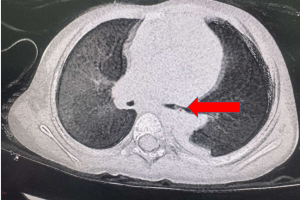

Quí phụ huynh lưu ý …coi chừng trẻ bị dị vật đường thở bỏ quên! Vừa qua bệnh viện Nhi đồng Thành phố , tiếp nhận một trẻ Ph. Kh. Ng, 25 tháng, nữ. khai thác...